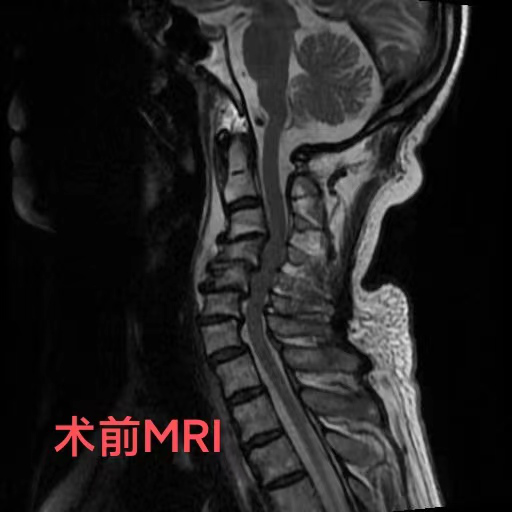

近日,74歲的陳爺爺,由于出現頸部疼痛、手腳麻木、行走困難等癥狀被家人送到重慶醫科大學附屬璧山醫院(重慶市璧山區人民醫院)康復醫學科就診。科室羅秋紅主治醫師為其進行了頸椎核磁共振檢查,結果提示,患者頸椎變形已導致脊髓神經受壓,隨時有高位截癱的風險。陳爺爺患有頸椎病多年,因擔心手術帶來的風險,長期依靠理療來緩解病痛,這次也是因為癥狀日趨嚴重,無奈之下才前來就醫。

羅醫生第一時間聯系了神經外科脊柱脊髓組的鄧雷主治醫師。針對陳爺爺及其家屬的擔憂,鄧雷主治醫師進行了耐心細致的溝通,最終陳爺爺決定配合醫護進行手術治療。患者高齡且有基礎疾病,手術方案需要慎之又慎。神經外科副主任(主持工作)徐忠燁主任醫師組織全科醫生根據患者具體病情,制定了最終方案:前路3節段頸椎間盤切除+頸椎后凸畸形矯正。

陳爺爺長期的頸椎變形產生了大量骨質增生,給術中的鄧雷、蔣登志醫生出了難題。在神經顯微鏡下,他們的眼睛如鷹,指尖之中飛舞最溫柔的神經刀鋒,雕塑著最堅硬的頸椎驁骨。最終,手術耗時兩個半小時,成功矯正,沒有神經損傷!患者術后3天康復出院。